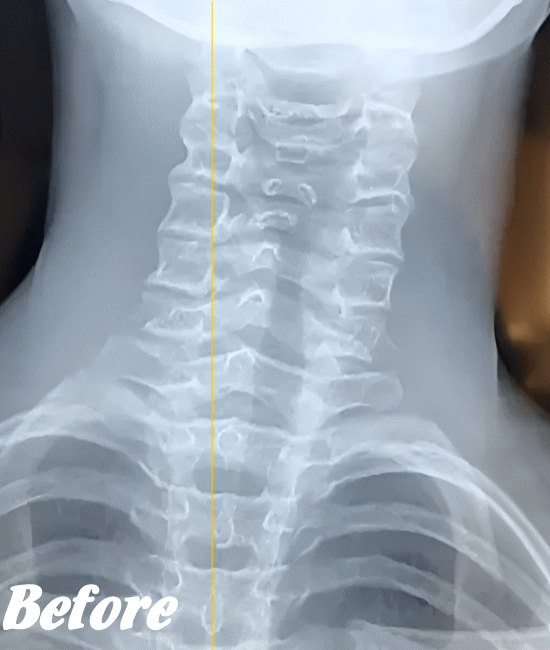

緊張型頭痛/肩こり頭痛の発生は、首背面の筋肉が緊張し血流が悪くなることが大きな原因だと考えられます。そこで、まずは首まわりや肩まわりの筋肉を緩め、潤滑な血行を確保させることを優先に施術します。

そのために、背骨の歪みを整え、肋骨、肩甲骨、首や首の付け根など、血流を阻害している部位の筋骨格をすべて調整します。